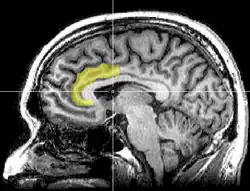

In recent years, psychologists have focused their attention on the neurological basis for violent games motivating aggression. Specifically, Weber, Ritterfield, and Mathiak (2006) conducted a within-subjects design to examine the influence of violent and non-violent video games on 13 male participants. The functional magnetic resonance imaging (fMRI) study found that the violent content of the video games suppressed the affect areas of the anterior cingulate cortex (ACC) and the amygdala. Conversely, there was activity in the cognitive area of the ACC.

The results indicate that the neural patterns that are responsible for controlling aggressive cognitions and behaviours are directly altered in the presence of VVG exposure. The influence that VVG's have on aggression can be attributed to the role of the ACC. The ACC is the area of the brain that regulates an individual's decision-making, empathy, and emotion. Therefore, through influencing an individual's neural patterns, violent games determine how an individual reacts to violent cues. Consequently, when exposed to VVG's this alters the neurological structure by increasing areas associated with aggressive cognitions and behaviours, and by decreasing empathy (desensitisation). Accordingly, this finding supports the cognitive component of the GAM, in addition to the desensitisation hypothesis. However, there is the possibility that the neural activity demonstrated in the study is due to the presence of fear activating the amygdala and not aggression.

Further support by Hummer et al., (2010) provides incremental evidence of the significance of neurology in determining whether VVG's motivate aggressive behaviour. This study used an fMRI to examine neurological changes in men and women during violent or non-violent video games. The study found that VVG exposure resulted in a lower response in an individual's dorsolateral prefrontal cortex (DLPFC). This finding is significant as the DLPFC is responsible for an individual's executive functioning, including the suppression of unwanted thoughts and feelings. Consequently, the lower inhibition by participants results in a susceptibility to aggression through individuals not being able to control their thoughts and feelings.

The significance of these neurological findings are that they provide researchers with the ability to make casual inferences in support of the hypothesis that VVG motivate aggression. In demonstrating the physiological changes due to the violent content in video games, neurological studies challenge opposition to the connection. Subsequently, the more accurate question may be to what extent VVG's motivate aggression, rather than attempting to determine whether there is an association or not.